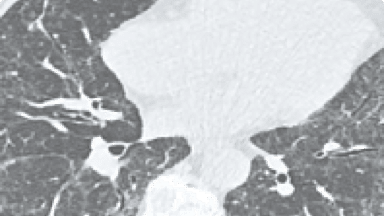

IDIOPATISK LUNGFIBROS

Idiopatisk lungfibros (IPF) är en sällsynt sjukdom som förkommer främst bland äldre och som kan ha snabbt förlopp med hög mortalitet